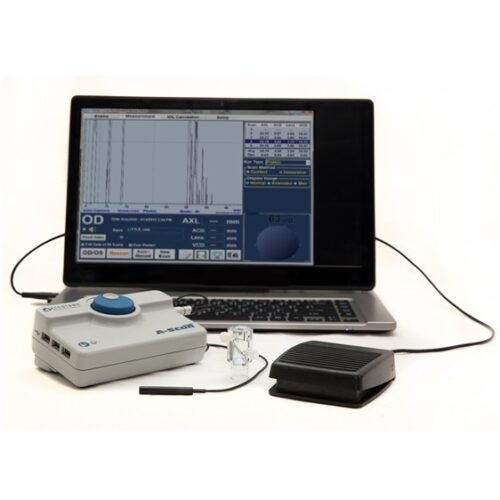

- A-SCAN, BIOMETRY

Small size, big features

With features including advanced movie mode technology, real-time image capture, a wide range of measurement and annotation tools and reporting capabilities and intuitive and easy-to-use software, Eye One™ delivers all the performance requirements you’re looking for in a practical form that also offers the convenience of portability should you need it.